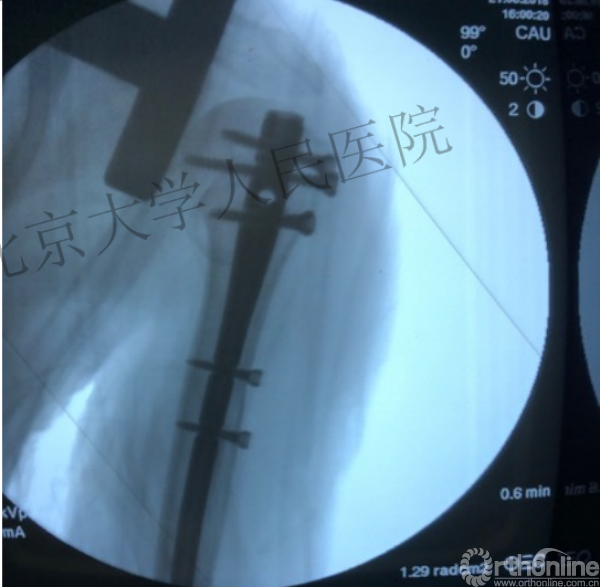

复位良好的标准:颈干角:135°,大结节与肱骨头距离:8mm

术后3月随访:继发性颈干角变小22°(5-82),肱骨头内翻,达46%

进钉更完美——我们的帮助

术中片